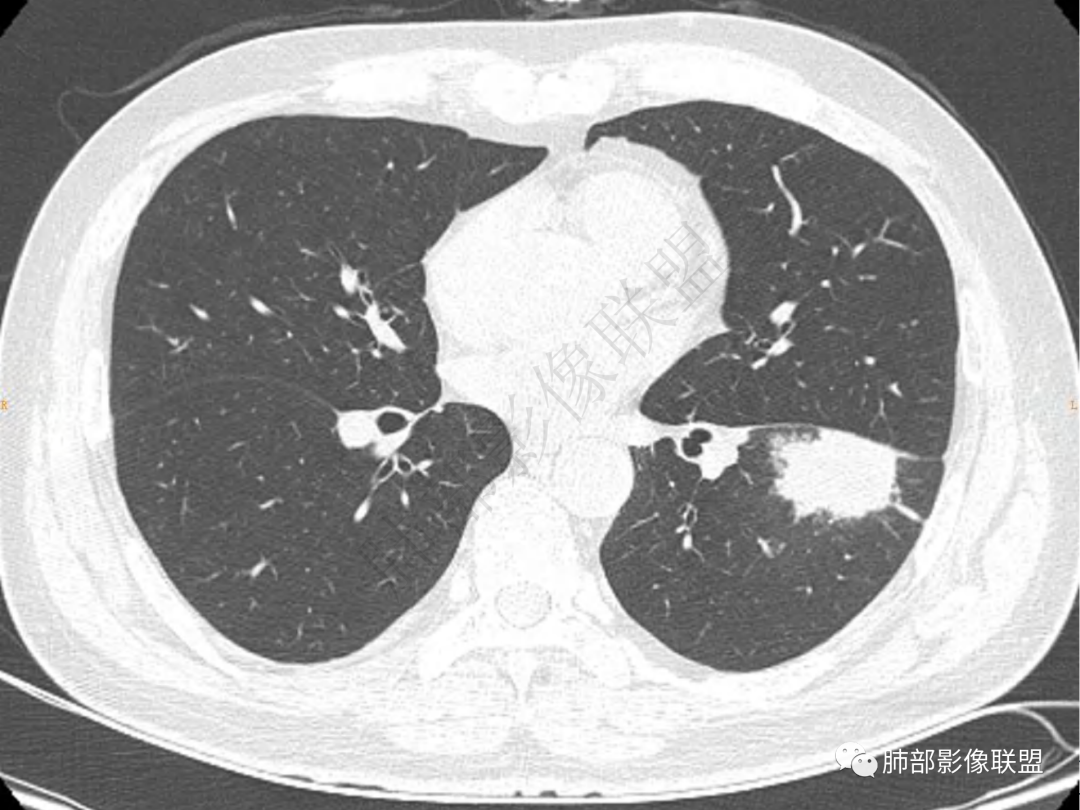

2.左肺下叶团片影,跨背段及内前基底段,实性部分类椭圆形,密度不甚均匀,可见毛刺及棘状突起,未见典型分叶及胸膜凹陷。病灶上下缘可见相应肺段支气管旁进侧出,管壁轻度增厚,未见狭窄阻塞。

3.周边较大范围磨玻璃影,边界相当模糊,小叶增厚明显。注意叶裂另一侧、左肺舌段亦可见磨玻璃影及增厚的小叶间隔。未见明确卫星病灶。

4.实性部分不均匀环形强化并显示一小范围低密度坏死区或空洞。较之肺窗,整体纵隔窗范围较小,提示病灶并不十分密实。抑或为不同时段图像。

肺脓肿:可宽基底与胸膜相连,附近胸膜增厚——炎性特点

肺脓肿:边界模糊不清,或者块影为类圆形,无明显分叶,边缘平直为主,刀切征——炎性特点三、病灶周围特点:肺脓肿:病灶非远端有片状GGO——炎性特点四、近端支气管阻塞:肺脓肿:常有引流支气管伴管壁增厚或者支气管沿洞壁走行。五:坏死壁:肺脓肿:大多壁厚,少数壁薄,没有壁结节,内壁清楚光整——炎性特点

肺脓肿:环形强化,强化较显著。如出现明显囊壁样强化甚至边缘“憩室”样突出,高度支持肺脓肿。